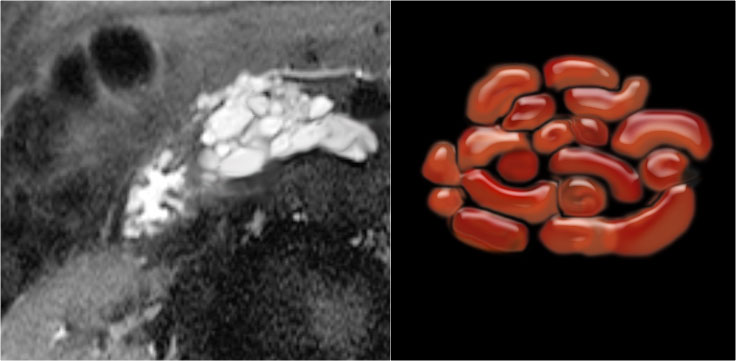

MRI better demonstrates the morphologic features of the lesion (fig).

On T2WI the lesion is multicystic.

Note the central low signal due to the central scar with calcifications.

Although some of the cysts are rather large, this is still a characteristic appearance of a serous cystic adenoma (macrocystic form).